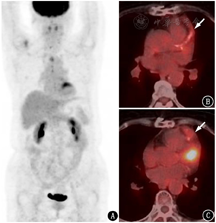

3.重要血管受累及PET假阴性的问题(图3,图4,图5)。大血管炎可以累及主动脉的各分支,重要的分支动脉受累可能引起相应症状。例如,本例患者的视野缺损和视力下降与上颌动脉受累相关;当冠状动脉受累时会产生心肌缺血相关症状(图3);颅内供血动脉受累可能产生脑缺血改变;腹部分支血管受累可能导致供血脏器缺血的表现(图4)。因此在图像判读时,对于不易观察的重要分支也要仔细辨认分析。

虽然文献报道18F-FDG PET/CT诊断大血管炎的灵敏度高[2],但在临床实践中,除了糖皮质激素的应用会导致假阴性,有时未经治疗且临床典型的大动脉炎/巨细胞动脉炎也会出现假阴性的PET结果(图5)。原因并不明确,也许与参与大血管炎的不同炎性反应通路有关。